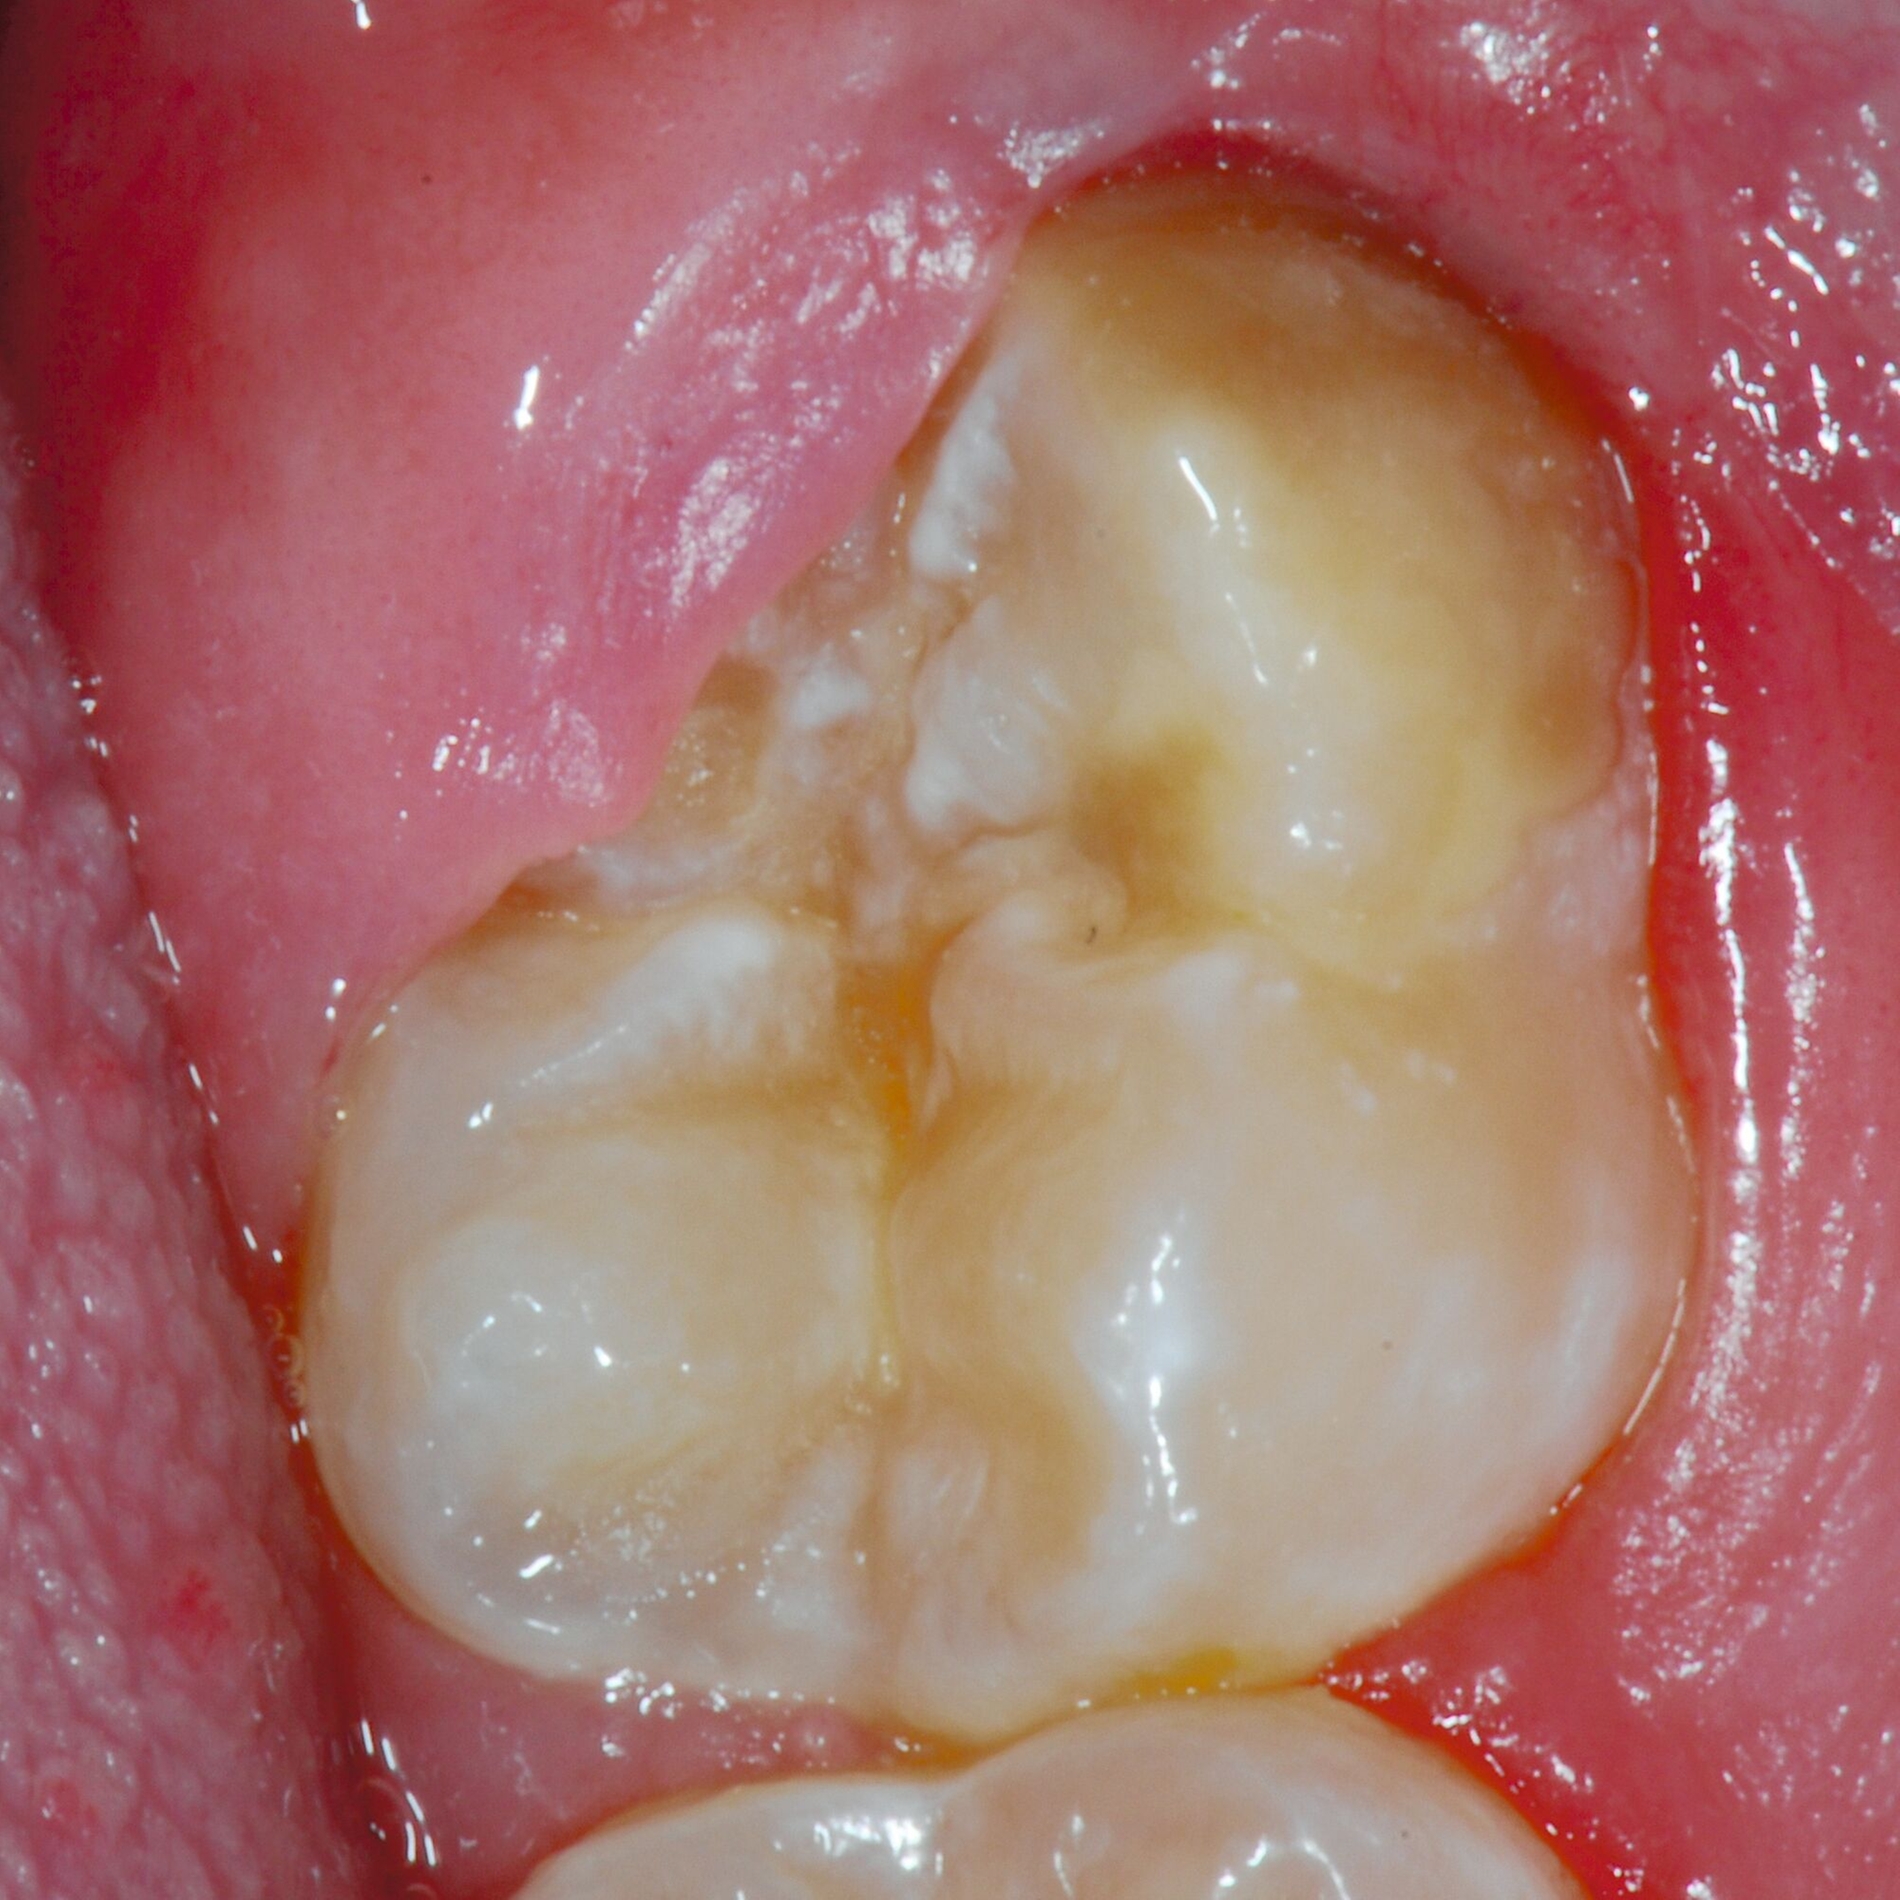

Das klinische Erscheinungsbild an bleibenden Zähnen zeigt typischerweise weißlich-gelbe bis gelblich-braune Opazitäten, die zumindest in einigen Bereichen durch eine scharfe Abgrenzung (engl.:„demarcated opacities“) zum gesunden Zahnschmelz charakterisiert sind (Abbildungen 3 und 4). Die abgegrenzten Hypomineralisationen befinden sich mehrheitlich im Bereich der inzisalen Kronenhälfte unabhängig von dem Auftreten an Front- oder Seitenzähnen. Die Ausprägung am Zahn kann dabei auf einzelne Areale oder Höcker begrenzt sein.

Bei einer schwerwiegenderen Ausprägung sind Zahnflächen vollständig betroffen, mitunter alle Zahnflächen an einem Zahn. Die Verteilung in der Dentition beziehungsweise an den Indexzähnen ist gleichermaßen variabel und betrifft nicht nur die Defektgröße, sondern auch die Farbe und Festigkeit. Was die Festigkeit betrifft, gilt als die Faustregel: Je dunkler die Farbe des Schmelzes, umso weicher beziehungsweise poröser und damit minderwertiger wird dessen Qualität sein. Damit reduziert sich seine kaufunktionelle Belastungsfähigkeit, was insbesondere an ersten bleibenden Molaren von klinischer Relevanz ist.

Für die Dokumentation und Klassifikation der MIH wurden verschiedene Systeme vorgeschlagen. Als historisch und veraltet gilt der (modifizierte) DDE-Index. Demgegenüber haben die Kriterien der EAPD – abgegrenzte Opazitäten (Abbildung 3 und 4), Schmelzeinbrüche (Abbildung 5), atypische Restaurationen (Abbildung 6) – mittlerweile die weiteste Verbreitung gefunden. Diese wurden 2003 erstmals zur Beschreibung der MIH auf empirischer Basis publiziert [Weerheijm et al., 2003] und den Jahren 2010 und 2022 im Rahmen der damaligen MIH-Workshops bestätigt [Lygidakis et al., 2010; 2022].